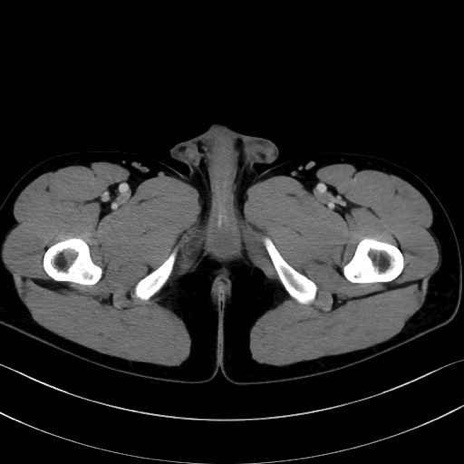

肛門挙筋 (Levator ani)